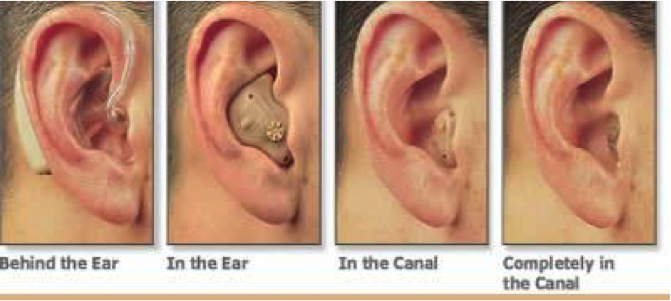

Современные слуховые аппараты при сенсоневральной тугоухости